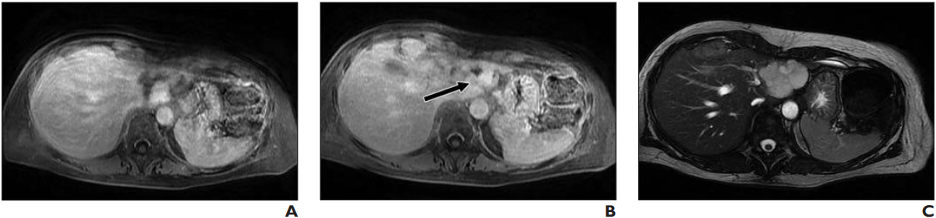

56-Year-Old Woman With Benign Hemangioma: Lesion was originally reported as indeterminate enhancing mass, and outside report recommended biopsy. Classic features of benign hemangioma are shown. Error was attributed to faulty reasoning. A, Axial MR image obtained 5 minutes after contrast agent administration shows peripheral nodular discontinuous enhancement. B, Axial MR image obtained 10 minutes after contrast agent administration shows centripetal progression of enhancement (arrow). C, Axial fast imaging employing steady-state acquisition (FIESTA) MR image shows lesion is homogeneously hyperintense compared with liver parenchyma.

The most common error type contributing to both overall and primary discrepancy was faulty reasoning (a cognitive error characterized by misidentifying an abnormality), which occurred in 34.3% of the total discrepancies (95% CI, 29.0– 40.0%) and 37.8% of the primary discrepancies.